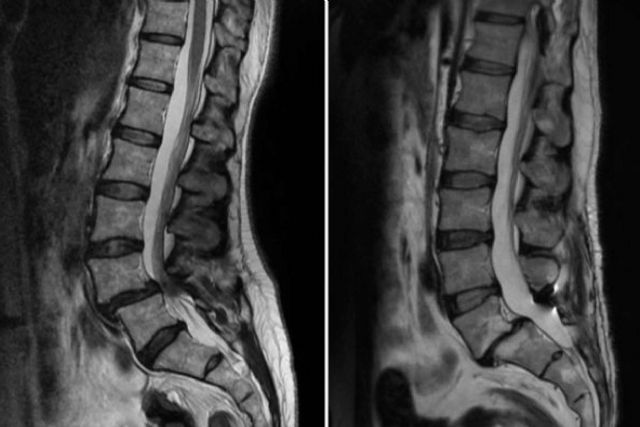

El diagnóstico de esta afección requiere varias pruebas. Las radiografías son útiles para obtener imágenes de la columna vertebral y localizar la vértebra afectada. La resonancia magnética (RM) es otra herramienta clave que ofrece imágenes detalladas de los tejidos blandos y estructuras vertebrales mediante un potente imán conectado a un ordenador. Por último, la tomografía computarizada (TC) sirve para crear imágenes tridimensionales de la columna, ayudando a visualizar el desplazamiento vertebral con mayor precisión.